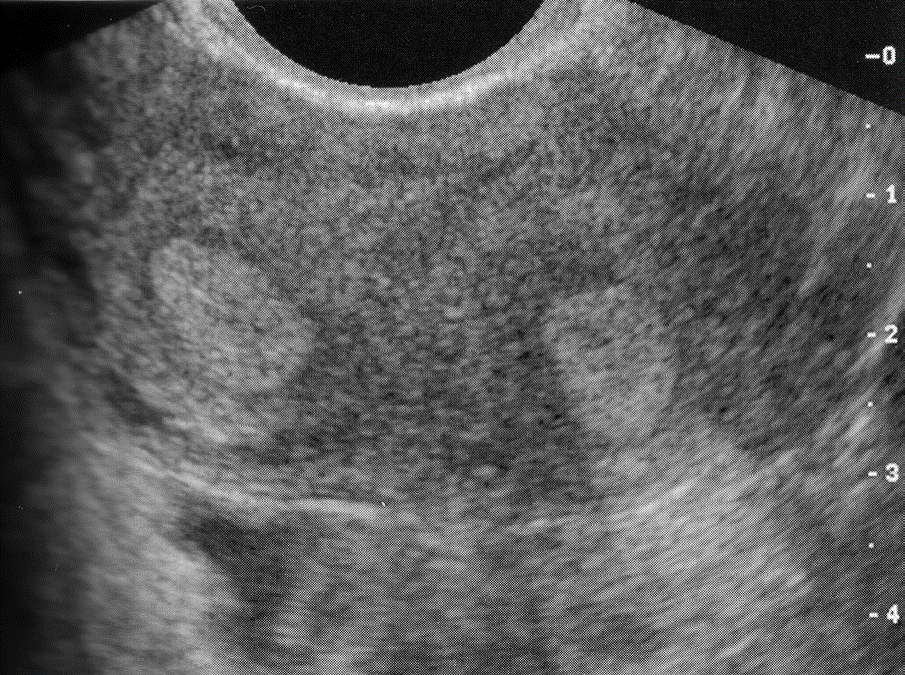

Uterus w/ Fibroids

submucosal fibroids